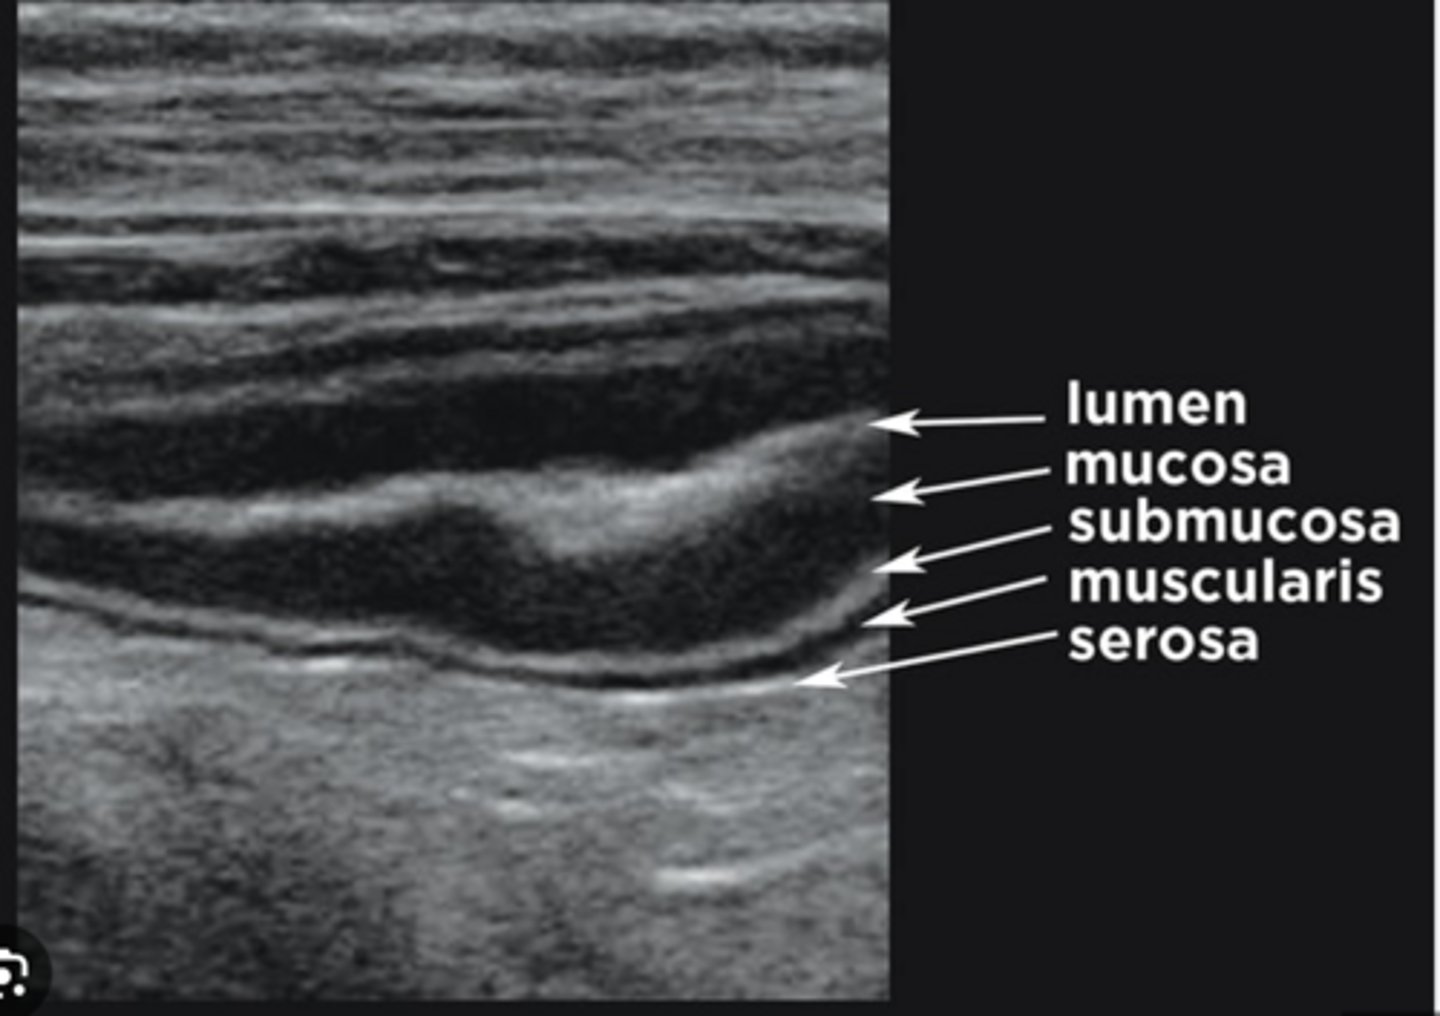

Serosa

Echogenic - Bright

Muscular Layer

Hypoechoic - Dark

Submucosa

Mucosa

Surface of Mucosa